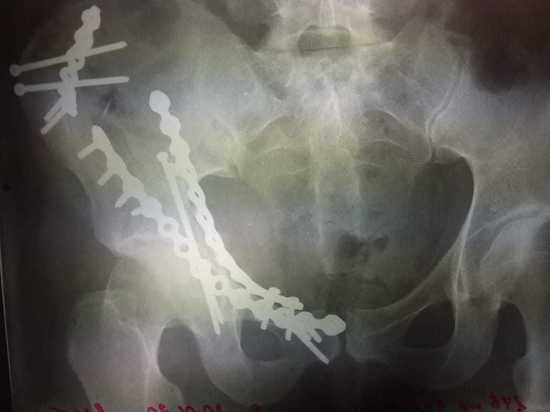

Типы переломов при авариях: советы по первой помощи